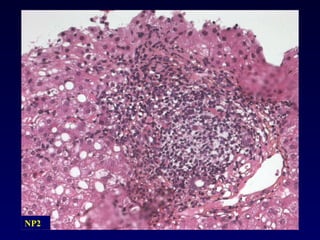

Infiltrat lymphocytaire portal diffus nodulaire caractéristique d’une hépatite chronique. Hépatite chronique - Lésions élémentaires

Destruction de la lame bordante par des cellules inflammatoires Evaluation de l’intensité - Extension: focale ou diffuse (/ espace porte) - Nombre d ’EP atteints La nécrose parcellaire est un marqueur d’activité de l’hépatite chronique Nécrose périportale Piecemeal necrosis Nécrose parcellaire Hépatite d’interface Hépatite chronique - Lésions élémentaires

NP2

NP2 NP2